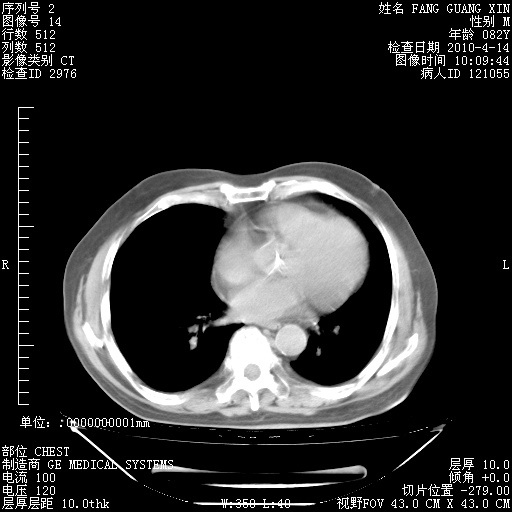

4月14日肺部CT

肺部CT平扫未见异常。